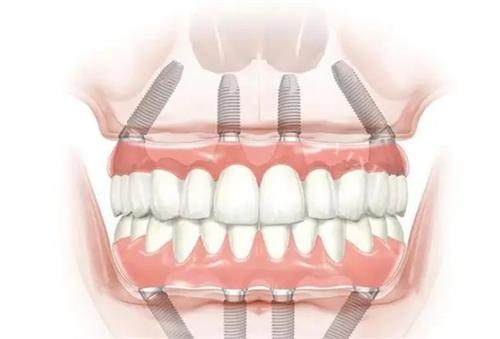

全口种植牙是指上下颌牙齿全部缺失后,通过植入人工牙根(种植体)来支撑固定全口义齿的修复方式。通常需要在上颌或下颌植入4-8颗种植体,然后在其上安装固定或可拆卸的义齿。

稳定性好:通过多个种植体固定,义齿不易松动

咀嚼功能强:接近天然牙的咬合力

舒适度高:无需传统义齿的基托

保护牙槽骨:防止骨量继续流失